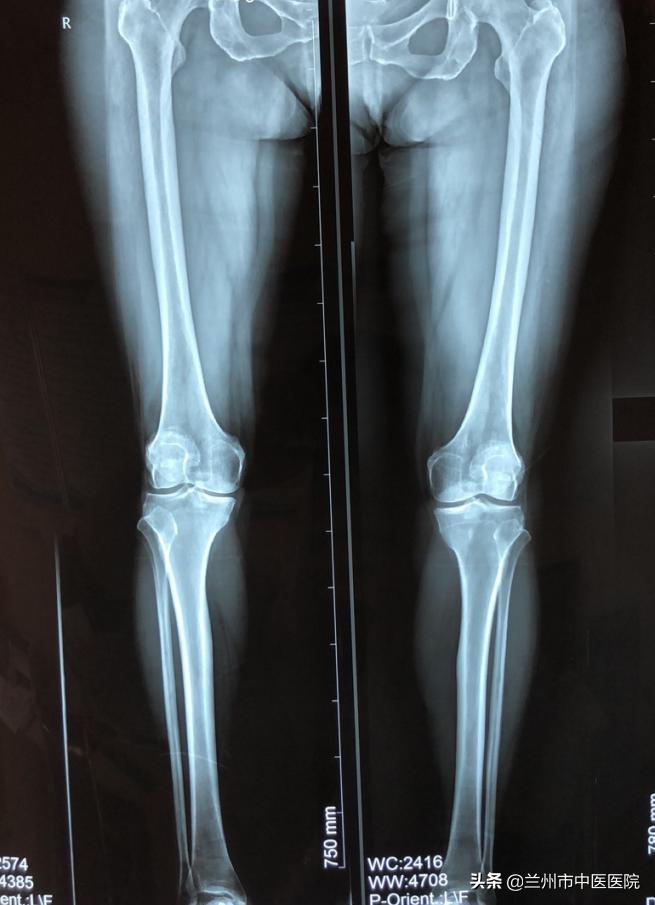

近日,兰州市中医医院骨科团队精诚合作,在麻醉科等相关科室的全力配合下,成功完成了单间室膝关节骨性关节炎、单髁置换术,手术顺利完成,病人术后恢复良好,家属满意。

近年来,全膝关节置换术(TKA)已经被证明是一种治疗膝关节骨性关节炎非常有效的手术。膝关节由三个间室组成:内侧间室(位于膝关节内侧),外侧间室(位于膝关节外侧)和髌股关节间室(位于膝关节的前面)。然而,在有些骨关节炎的患者中,骨关节炎不会累及整个膝关节,只有内侧间室可能会受到疾病的影响。对于这些患者,单髁关节置换是可以选择的治疗方法。膝关节单髁关节置换(UKA)已成为某些患者的可行选择。

膝关节的单髁置换手术,仅把膝关节的单侧髁部置换为表面假体。把膝关节由前正中线上等分,单侧髁部就是内侧或者是外侧的部分。简单来说,就是对一半膝关节进行置换,这一半膝关节主要构成是胫骨髁和股骨髁。当患者膝关节因骨性关节炎等发生了的严重病灶,但病变范围比较局限,该手术可以保留2/3正常的膝关节结构,让患者可以保留关节自然本体的感觉,恢复关节的活动,还可以延缓患者做全膝关节置换的时间。